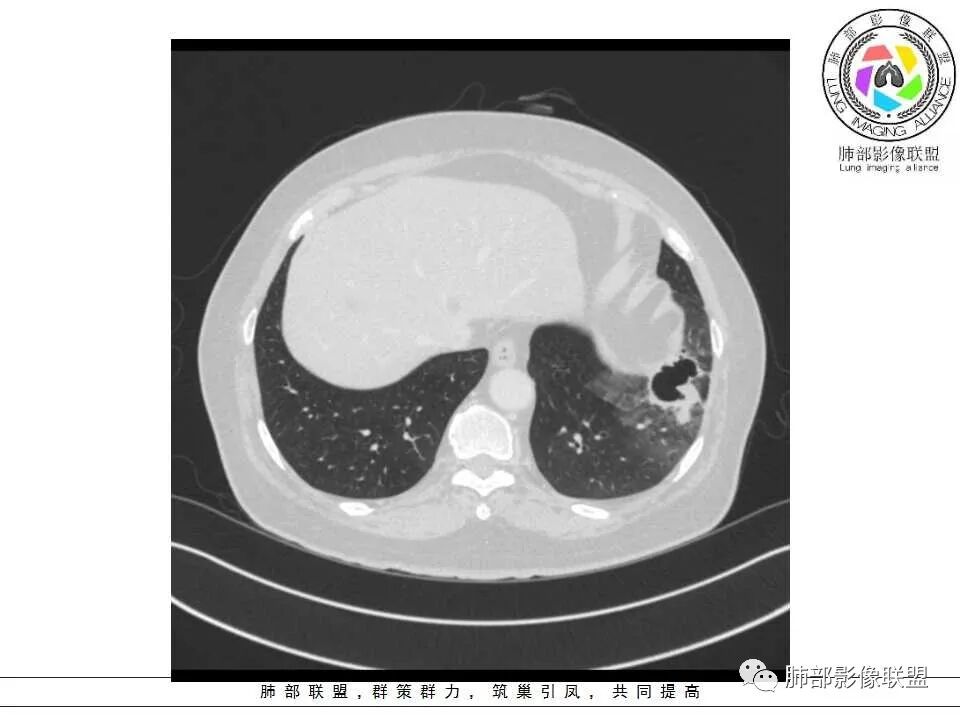

女性,65岁,左肺下叶空腔边缘见不规则结节,结节强化轻、不均匀,局部坏死边界较清楚,胸膜为糊墙为主,膈面胸膜判断不清楚似有结节;空腔内见分隔,或者数个融合,局部张力稍弱,边缘见支气管截断和血管集束;外周见大片磨玻璃影,部分边界模糊。结合病史炎症肯定有,但是囊腔结节这部分感觉恶性征象多过良性,考虑囊腔型腺癌可能性大,鉴别肺大疱感染

左肺下叶囊性空腔影,内分隔,壁不均匀,周围磨玻璃边界清楚,胸膜牵拉。倾向腺,鉴别真菌感染。

胸CT:左肺下叶囊腔,壁厚薄不均,可见壁结节,囊腔内可见断裂小梁,部分融合,周围边界较清楚GGO,胸膜牵拉,可见血管集束、支气管充气征,冠状位部分层面可见支气管在囊腔边缘截断。考虑:囊腔型腺Ca。鉴别:肺大疱感染,CPAM等。

左肺下叶多发大小不等的空腔影,呈蜂窝状改变,内有分隔,壁增厚(硬壳,僵硬感觉),远端见斑片状密度增高影,边缘不清,与临近胸膜粘连。近肺门侧见支气管与空腔相连,部分相通,部分阻塞。病变周围见磨玻璃影,以肺门侧为诸,呈分叶状,大部分界清。建议抗炎治疗后复查除外囊腔型腺癌

病灶分两部分

周围大片GGO

中央囊实性病变

1、左肺下叶外基底段不规则囊腔样病灶,囊腔内有条形影及血管穿行。

3、灶周环以大范围磨玻璃影,非常均匀,没有重力分布趋势,分叶状,边界隐约可变。